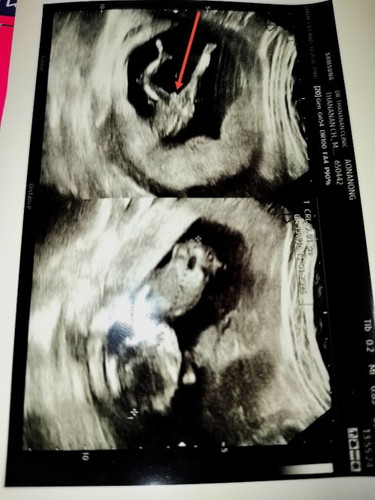

เมื่อใบซาวด์เห็นคล้ายจู๋แต่ผลNIPTบอกไม่เจอค่าy

ผล nipt ไม่ผิดพลาดค่า 99.99% เลย บ้านนี้ภาพอัลตราซาว ตรงตามผล nipt ค่า ยังไงให้คุณหมอลองอัลตราซาวดูใหม่เนาะ อาจจะเป็นมุมที่ทำให้ดูคล้าย แต่ไม่ใช่จู๋ค่า แนบภาพลูกชายประกอบค่า เผื่อเทียบกับของแม่

ตอนซาวอาจจะมีความเป็นไปได้ที่สายสะดือมาพาดแถวๆนั้น ทำให้มองเหมือนจู๋ค่ะ เชื่อผลนิฟค่ะ

ในภาพซาวน์มองเป็นกลีบนะคะ ถ้าชายจะเป็นอัณฑะกลมๆ นูนขึ้น และมีไข่ชี้ค่ะ